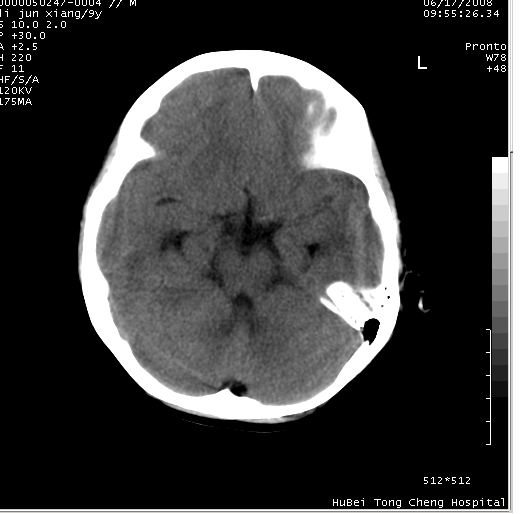

患儿 男,9岁。既往有“脑积水,脑萎缩?”病史(无影像检查资料),现无明显不适。其家长要求ct检查。

颅脑ct轴位平扫(层厚、层距均为10mm),图像如下: